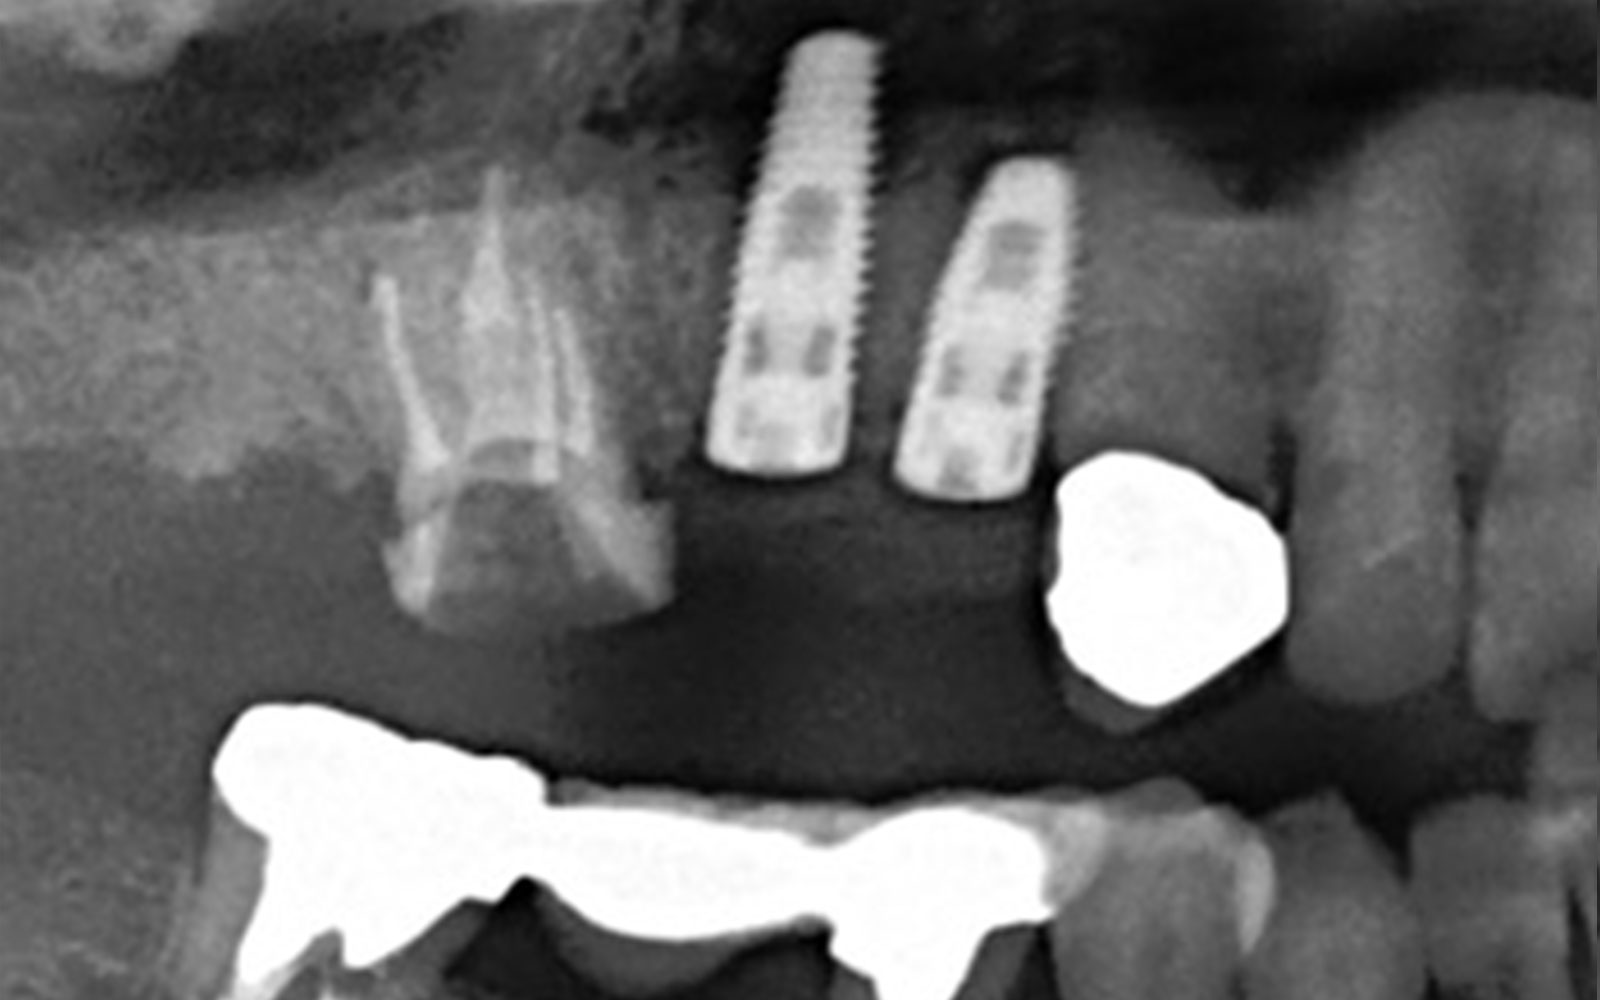

初診時

この方も左下4番の歯根破折です。7番目の歯は歯周病でグラグラな状態なのでインプラント2本埋入してます。

埋入後すぐに仮歯を入れたので術後当日より物が咬めるようになりました。